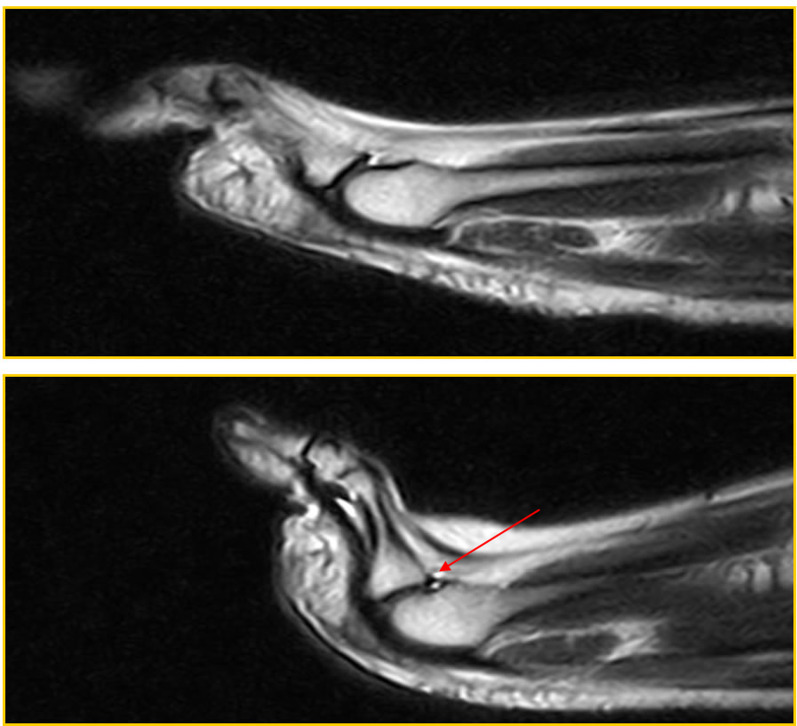

Materials and methods: All patients underwent forefoot MRI (Atroscan C, Esaote, Genoa, Italy), operating at 0.2 T. All patients first underwent a standard MRI examination (coronal T1 and T2 weighted image (WI) with fat suppression and axial and sagittal T2 WI); the examination was completed by performing a stress test (hyperextension of toes). The ST is an easy task to perform and is not time-consuming (requiring only one additional sagittal fast spin echo (FSE) T2-weighted MRI sequence; repetition time/ echo time (TR/TE): 3200/90 ms) for patients and operators. A 45°-dorsiflexion ST was performed for approximately 2.30 min, the time required to complete the sequence. No further diagnostic investigations were necessary; no patients underwent arthrography or arthro-MRI. The examinations were performed in a double-blind mode by two operators with proven experience in musculoskeletal radiology; no cases of intra-operator discordance were found.

Results: Twenty-five patients were recruited into our study over a 2-year period; 15 were positive for metatarsal pain and 10 were controls. Before treatment (surgery), all patients displaying symptoms underwent evaluation. As a result, the imaging features accurately represented the natural and actual conditions of the lesions. Among the symptomatic patients, 11 out of the 15 exhibited a PP tear or dysfunction in both the standard position and the ST. Additionally, two out of the 15 individuals displayed a tear in the ST alone, with no indication of it in the standard position. In contrast, two out of 15 patients showed no evidence of a PP tear in either the standard position or the ST. However, these two patients demonstrated dorsal subluxation during the ST, likely due to micro-instability resulting from PP failure. In the asymptomatic patients, nine out of the 10 individuals were found to be negative for PP dysfunction. Only one out of the 10 patients exhibited dorsal subluxation solely in the ST, indicative of plantar plate dysfunction, but no evidence of a tear in the PP. In the asymptomatic patients, standard MRI provided a specificity of 100% and a high negative predictive value (NPV) (90%), while the latter increased with the ST (specificity and NPV equal to 100%). In symptomatic patients, standard MRI gave a sensitivity of 75% when assessing a PP tear, which increased to 100% with the ST; the sensitivity of standard MRI the evaluation of MF subluxation was 60%, but it reached 100% with the ST.